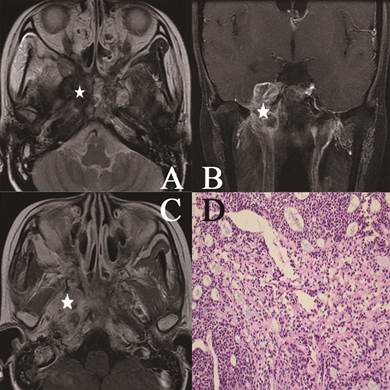

Figure 1

Head and neck MR images from a 25-year-old female with NACC. (A) Axial plane, T2-weighted image; (B) coronal plane, T1-weighted image after contrast medium administration; (C) Axial plane, T1-weighted image after contrast medium administration; (D) The characteristic eosinophilic basement membrane material in pseudocysts. True glands lined by cuboidal epithelium were visible (hematoxylin-eosin, original magnification ×200). The lesion invaded to the pterygopalatine fossa, the parapharyngeal space, the pterygoid process and the skull base representing isosignal intensity on the T2-weighted image (white star), high signal intensity on the contrast-enhanced T1-weighted image (white star). There were mixed hypointense, isointense, and hyperintense in the lesion (white star).

Figure 2

Head and neck MR images from a 51-year-old female with NACC. (A) Axial plane, T1-weighted image after contrast medium administration; (B) coronal plane, T1-weighted image after contrast medium administration; (C) Axial plane, T1-weighted image; (D) Cribriform growth pattern displaying several prominent pseudocysts surrounded by basaloid cells (hematoxylin-eosin, original magnification ×200). The lesion invaded the parapharyngeal space, the sphenoid sinus, the petrous apex and the muscles on the contrast-enhanced T1-weighted image without enhancement on the image (white star). On the T1-weighted image, the lesion represented low signal intensity invading the nasal cavity, the parapharyngeal space (white star).